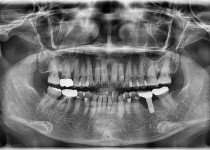

만 52세 전악 상악, 하악 전체 임플란트…

만 56세 상 하악 임플란트 증례